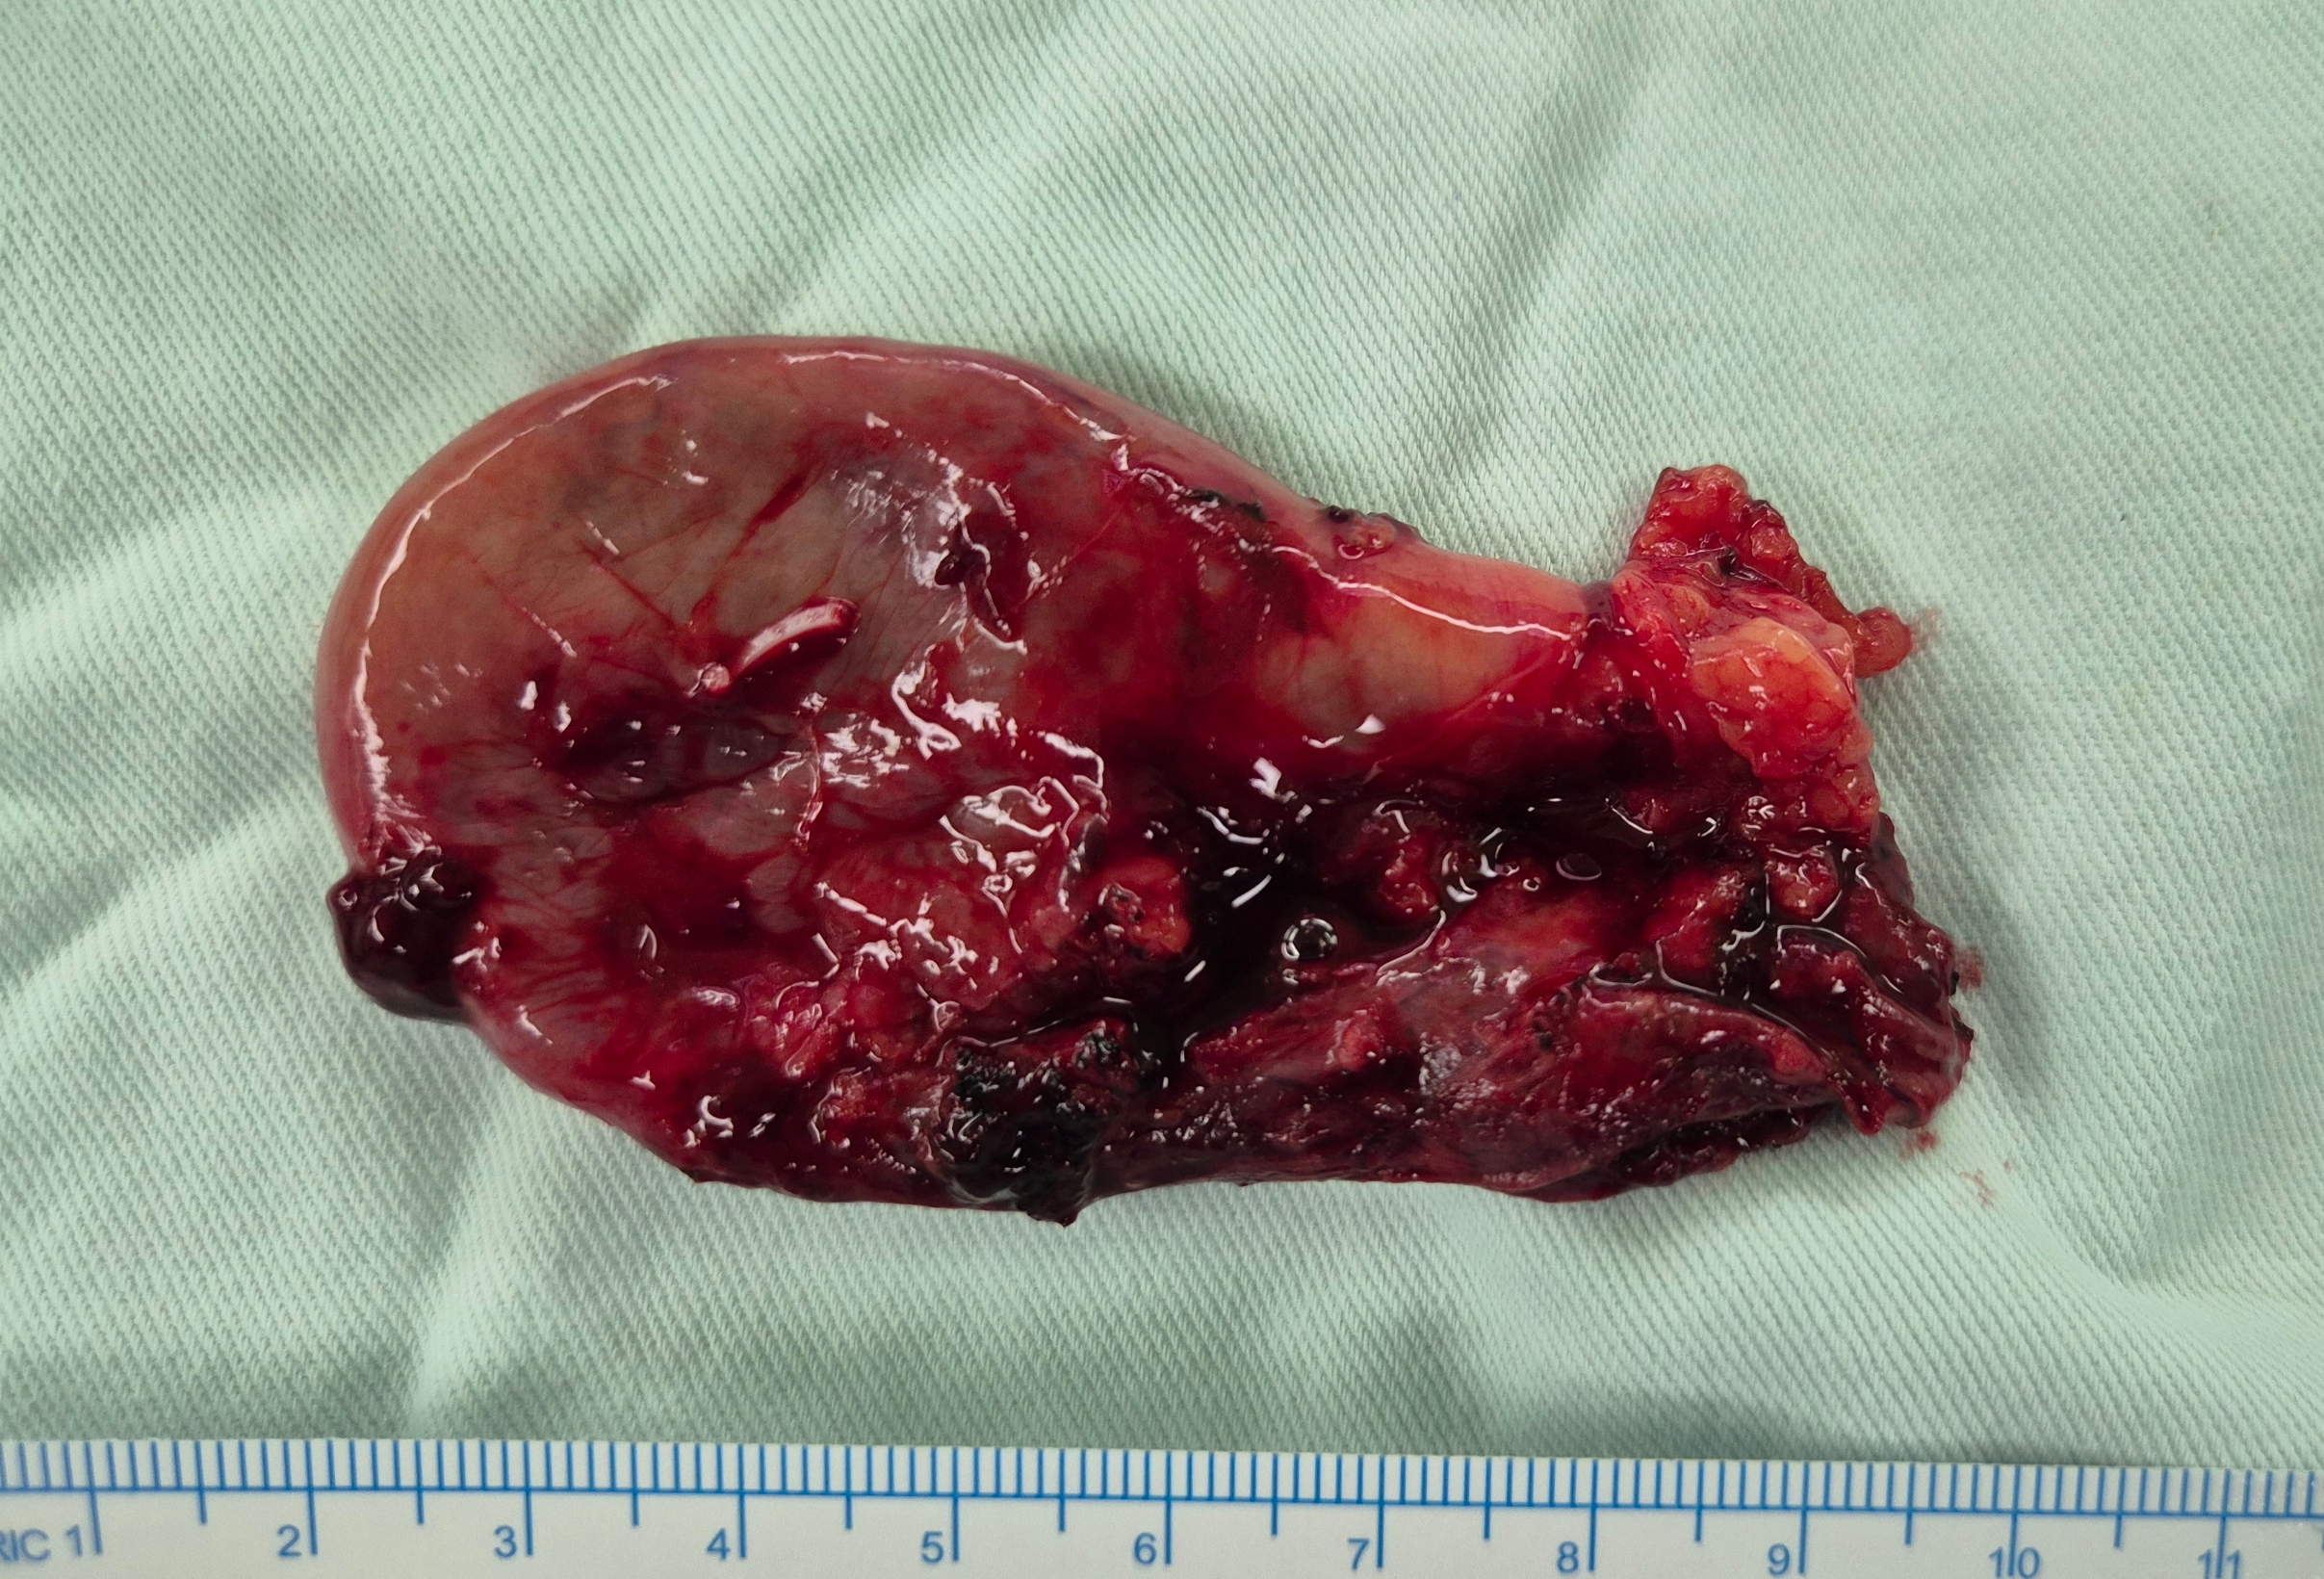

상복부 통증으로 응급실에서 진료보신 분으로 급성 담낭염으로 확인되어,

방금 복강경 담낭절제술을 시행했습니다.

수술은 40분 걸렸습니다.